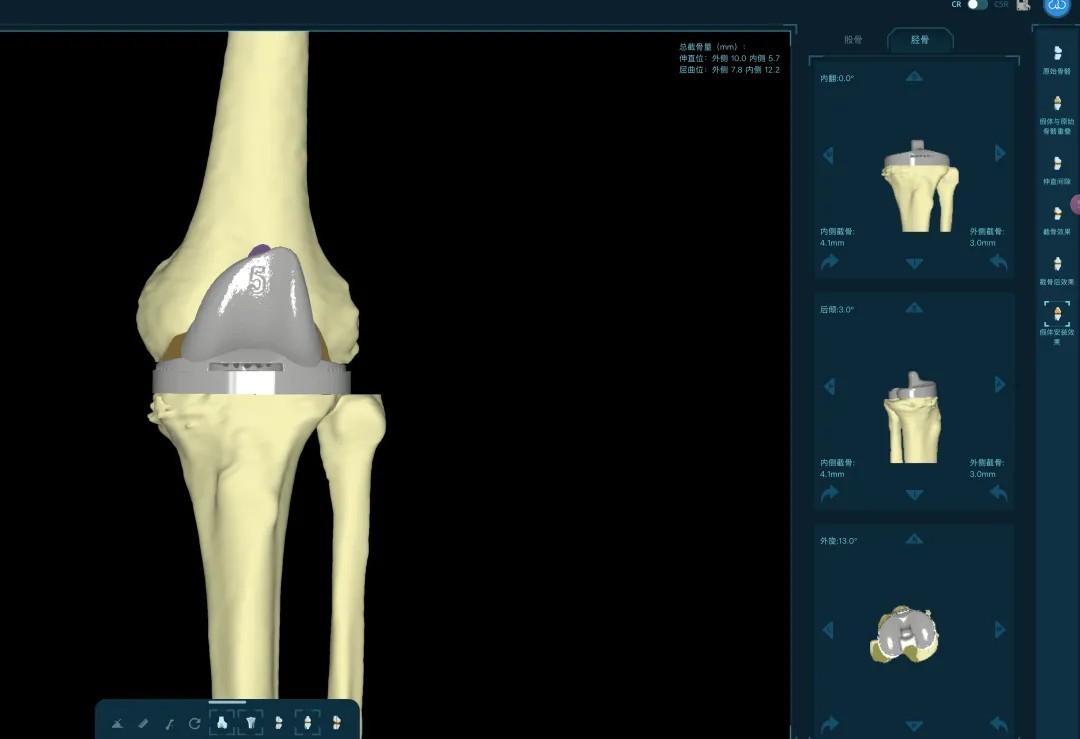

通過(guò)患者的CT數(shù)據(jù),系統(tǒng)構(gòu)建出膝關(guān)節(jié)的三維數(shù)字模型,精確評(píng)估骨缺損的范圍與形態(tài)。醫(yī)生可以在虛擬空間中,提前模擬手術(shù)過(guò)程,為患者“量體裁衣”,規(guī)劃出假體安放的最佳位置、角度以及所需填充骨缺損的特殊墊塊型號(hào)。

“這相當(dāng)于在真實(shí)戰(zhàn)斗前,進(jìn)行了一次全方位的沙盤推演。”羅軍介紹,這種規(guī)劃確保了手術(shù)的精準(zhǔn)度,縮短了手術(shù)時(shí)間,也為使用先進(jìn)的翻修假體系統(tǒng)做好了完美鋪墊。

本次手術(shù)的核心,是采用了Evolution® ECCK膝關(guān)節(jié)翻修系統(tǒng)。該系統(tǒng)專為應(yīng)對(duì)翻修手術(shù)中常見的嚴(yán)重骨缺損、韌帶功能不全等極端復(fù)雜情況而設(shè)計(jì)。

其模塊化的組件提供了前所未有的靈活性,就像一套高精度的“工程套件”,允許醫(yī)生在術(shù)中根據(jù)實(shí)際骨缺損情況,自由組合不同尺寸的墊塊、延長(zhǎng)桿等部件,實(shí)現(xiàn)關(guān)節(jié)線和力學(xué)穩(wěn)定性的個(gè)體化重建。